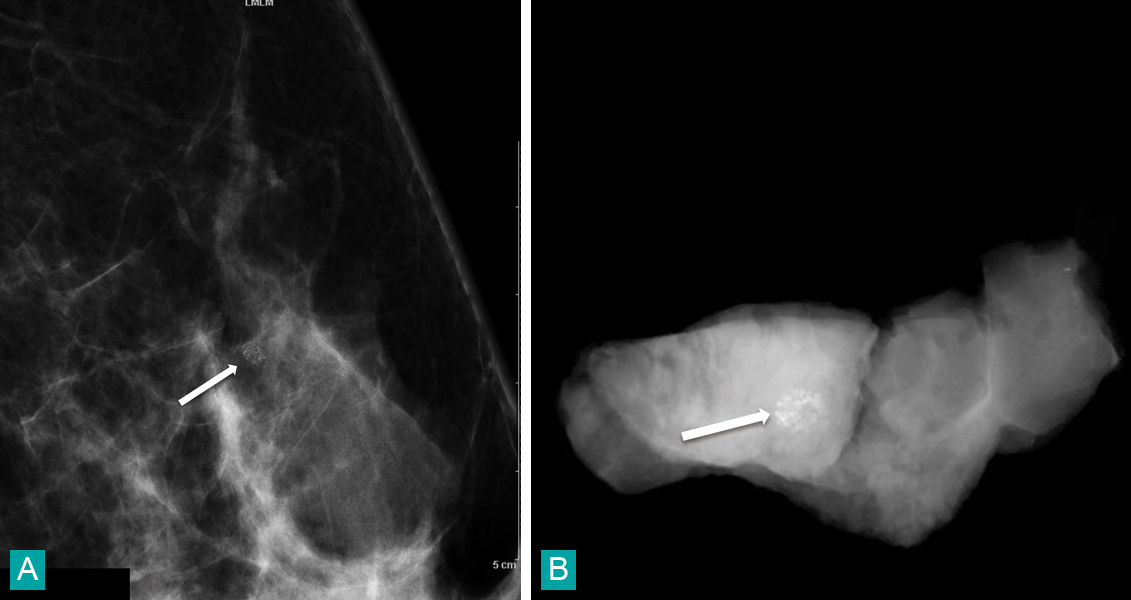

Patiente âgée de 59 ans chezqui l’on découvre l’apparition d’un foyer arrondi de microcalcifications dans le quadrant supéro-externe du sein gauche. Ce foyer apparaît dans le quadrant supéro-externe du sein gauche. Il est analysé à l'aide d'un cliché complémentaire en profil agrandi (fig. A), on le visualise au centre de l'image (flèche). Le radiologue le classe BI-RADS 4a et préconise la réalisation d'une macrobiopsie stéréotaxique. Cette biopsie est réalisée par un système d'ablation "monobloc" (Intact). On visualise le foyer de microcalcifications au sein de la carotte biopsique radiographiée (flèche) avant son envoi au laboratoire d'anatomopathologie (fig. B). L'analyse révèle un carcinome canalaire infiltrant.